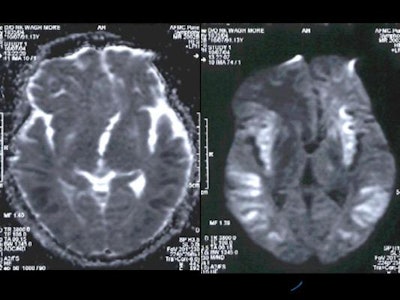

On diffusion-weighted images, there were hyperintense signals in the basal ganglia which appeared hyperintense on ADC maps, which implied that there was no restriction of diffusion in basal ganglia. However, the cortical grey matter showed hyperintense signals which appeared hypointense on ADC maps which indicated true restriction of diffusion [Figure 5].